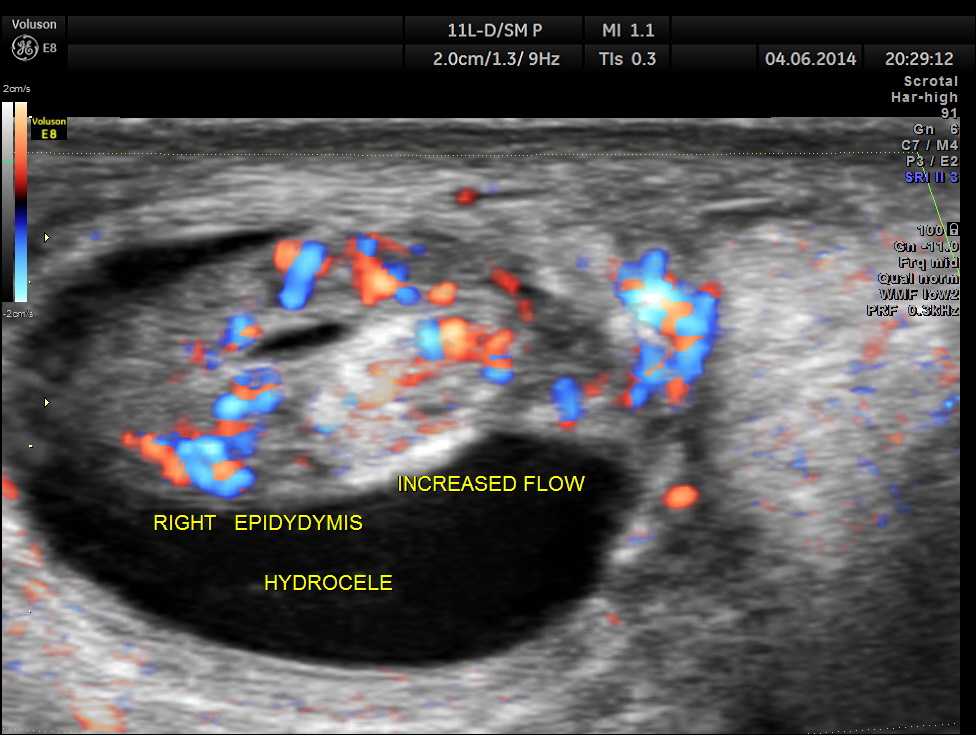

This was a 9-year-old boy , who was referred for evaluation of acute right scrotal pain of 2 days onset. He had mild right scrotal swelling and severe pain . One of the best uses of colour Doppler is for evaluation of acute scrotal pain , when the surgeon wants to rule out acute torsion . The other common condition is acute inflammation , which is medically managed. The images with colour just tell the story .

Rt Testis has normal appearance , with enlargement of the right epididymis . Colour flow imaging shows normal flow in the scrotum and increased flow in the epididymis , suggestive of acute inflammation – Acute Epididymitis.

Mild hydrocele is also seen.

This was a case of acute epididymitis , without orchitis . In our part of the world filarial infestation leading to acute epididymitis is a common occurrence .